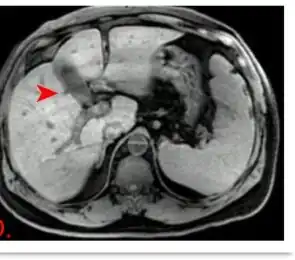

| Hepato-Splenomegaly characteristic of Stauffer syndrome (gallbladder and hepatic biliary ducts not dilated) | |

Stauffer syndrome causes abnormal liver function tests, especially those that reflect the presence of cholestasis, i.e. abnormal bile flow. Hepatosplenomegaly may also be observed. The symptoms and signs resolve if the renal cell carcinoma (or another associated tumor) is successfully ablated. It is due to release of IL-6 from cancerous cell.[1]